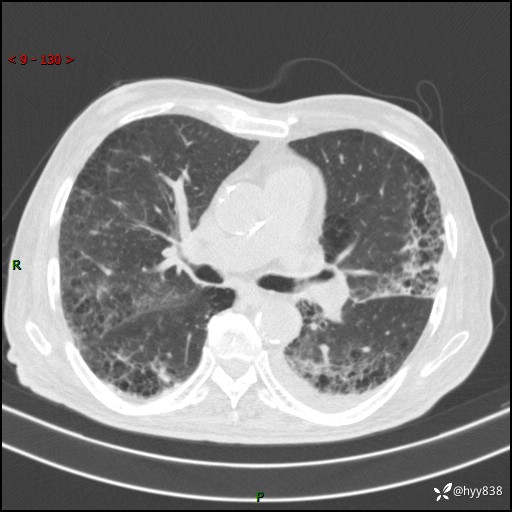

老年男性,间断咳嗽咳痰20余年,加重伴发热1天。呼吸科疑难病例讨论---结果公布

主诉:间断咳嗽咳痰20余年,加重伴发热1天

简要病史:家属代诉患者于20余年前无明显诱因出现咳嗽咳痰,痰为白色泡沫状,未行特殊治疗,不伴胸痛、胸闷、气喘、咳血等不适,1天前上午患者无明显出现发热,查体温39℃,伴咳嗽,咳痰无力,自行予以物理降温对症治疗,今晨2点左右再次出现发热,体温达40℃,自行服用复方氨酚烷胺对症治疗,凌晨3点左右复测体温38.2℃,现患者为求进一步诊治于今日就诊于我院门诊,行胸部CT提示双肺感染,遂以“肺部感染”收入我科。 患者本次起病来精神、食欲、睡眠欠佳,体力下降,体重无明显变化。

辅助检查:CT

胸部CT平扫